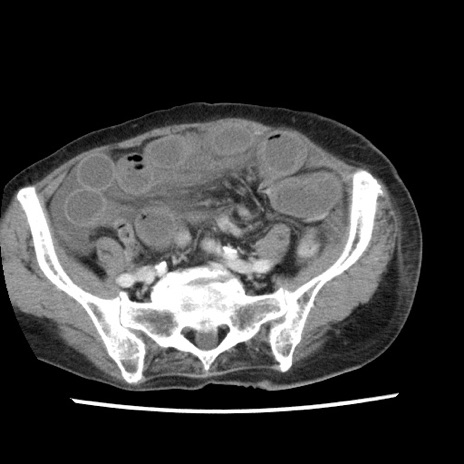

症例1(横断像)

【症例】80歳代女性

【主訴】腹痛

【現病歴】8時間前から腹痛あり来院。

【既往歴】糖尿病、脂質異常症、子宮体癌にて子宮全摘術

【身体所見】意識清明・会話良好だが腹痛で苦悶様、全腹部にわたって反跳痛と圧痛あり

【データ】WBC 13600、CRP 0.14、LDH 224、CK 90